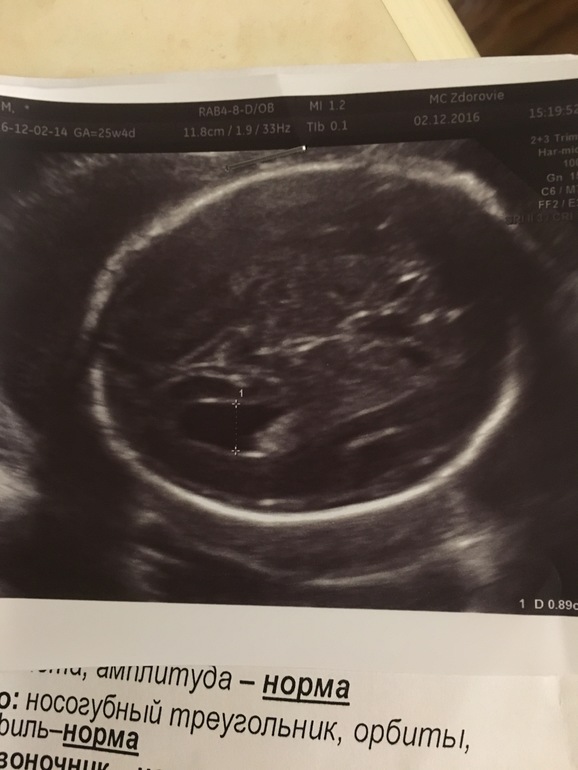

Узи в 25.4 нед.

УЗИ, КТГ, доплерСкажите пожалуйста все ли в порядке ? Интересует затылочный рог. Узистка сказала, что увеличен. Но до конца Б пройдёт .нервничаю со вчерашнего дня 😭😭😭 у кого так было и прошло ли потом ?